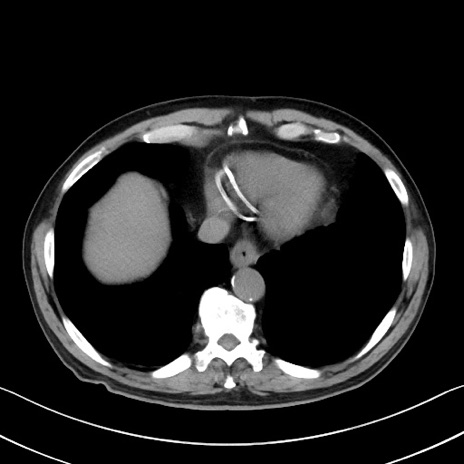

症例35(横断像)

【症例】70歳代 男性

【主訴】腹部膨満、嘔吐

【現病歴】昨日より腹部膨満感出現。本日増悪し、仙痛出現。嘔吐あり、受診。

【既往歴】糖尿病、胆摘後

【身体所見】BP 149/80mmHg、HR 74/min、BT 35.9℃、腹部:膨満、軟、圧痛なし。腸雑音減弱あり。上腹部正中切開瘢痕あり。

【データ】WBC 13500、CRP 1.72